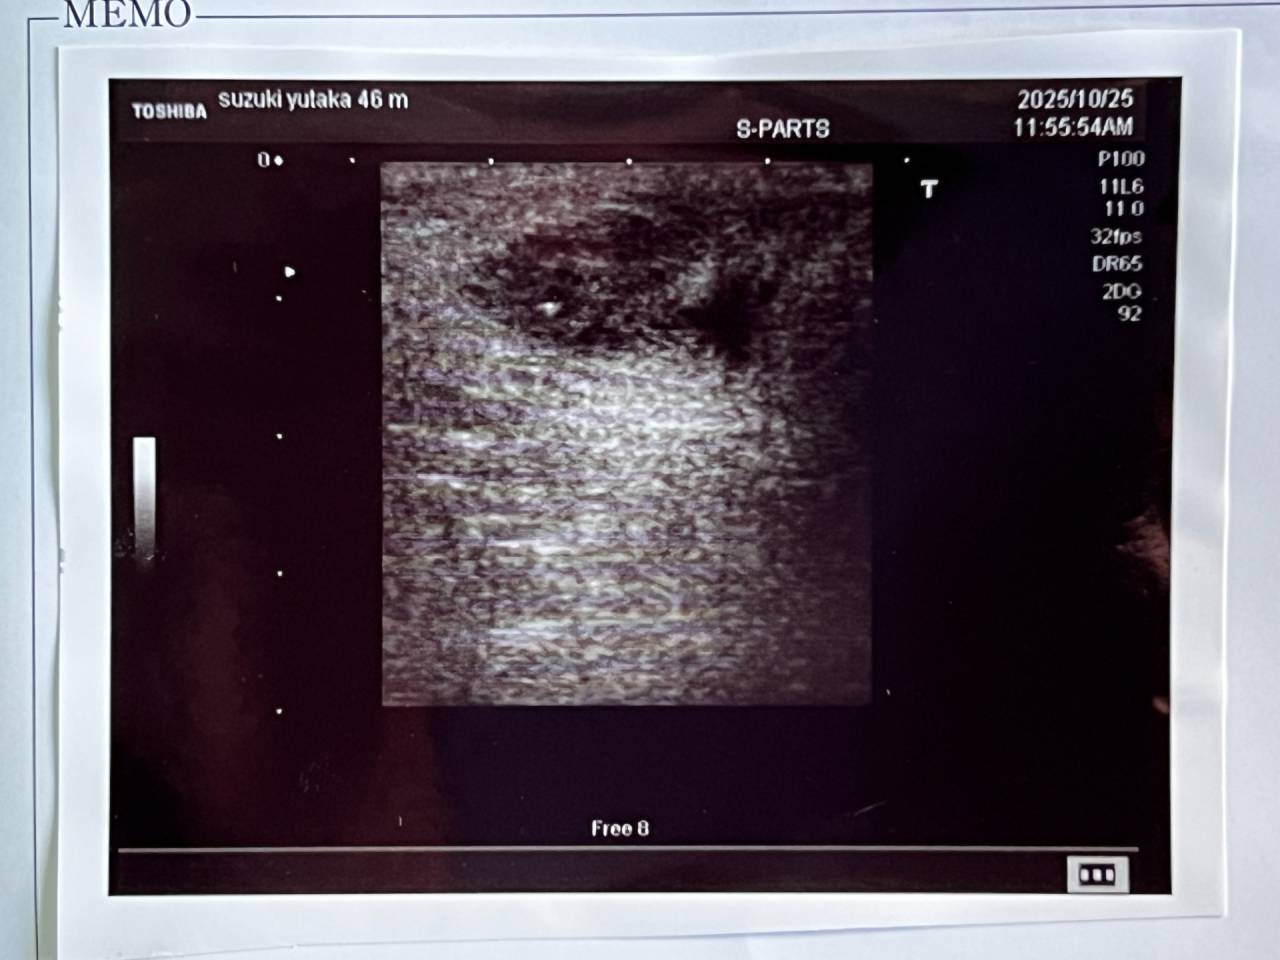

痔ろうとは、肛門周囲の皮膚と直腸の間にトンネル(瘻管)ができる「あな痔」とも呼ばれる病気です。初期には「肛門周囲膿瘍」という膿がたまり、痛みや腫れ、発熱などの症状が出ます。この膿が自然に排出されるか切開によって膿が出た後も、トンネルが残ることで繰り返す炎症や膿の原因となります。根本的な治療には手術が必要で、自然治癒はしません。

黒い部分が膿です。